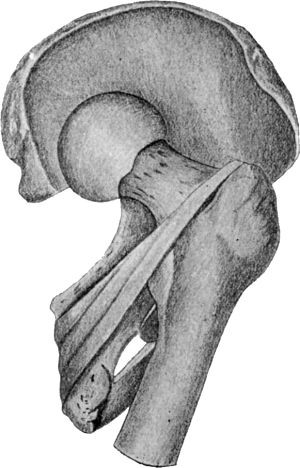

29 12.Os Innominatum showing new Socket formed after Old-standing Dislocation

Diagram of the most Common Dislocations of the Hip

142 72.Dislocation of Right Femur on to Dorsum Ilii

143 73.Dislocation on to Dorsum Ilii